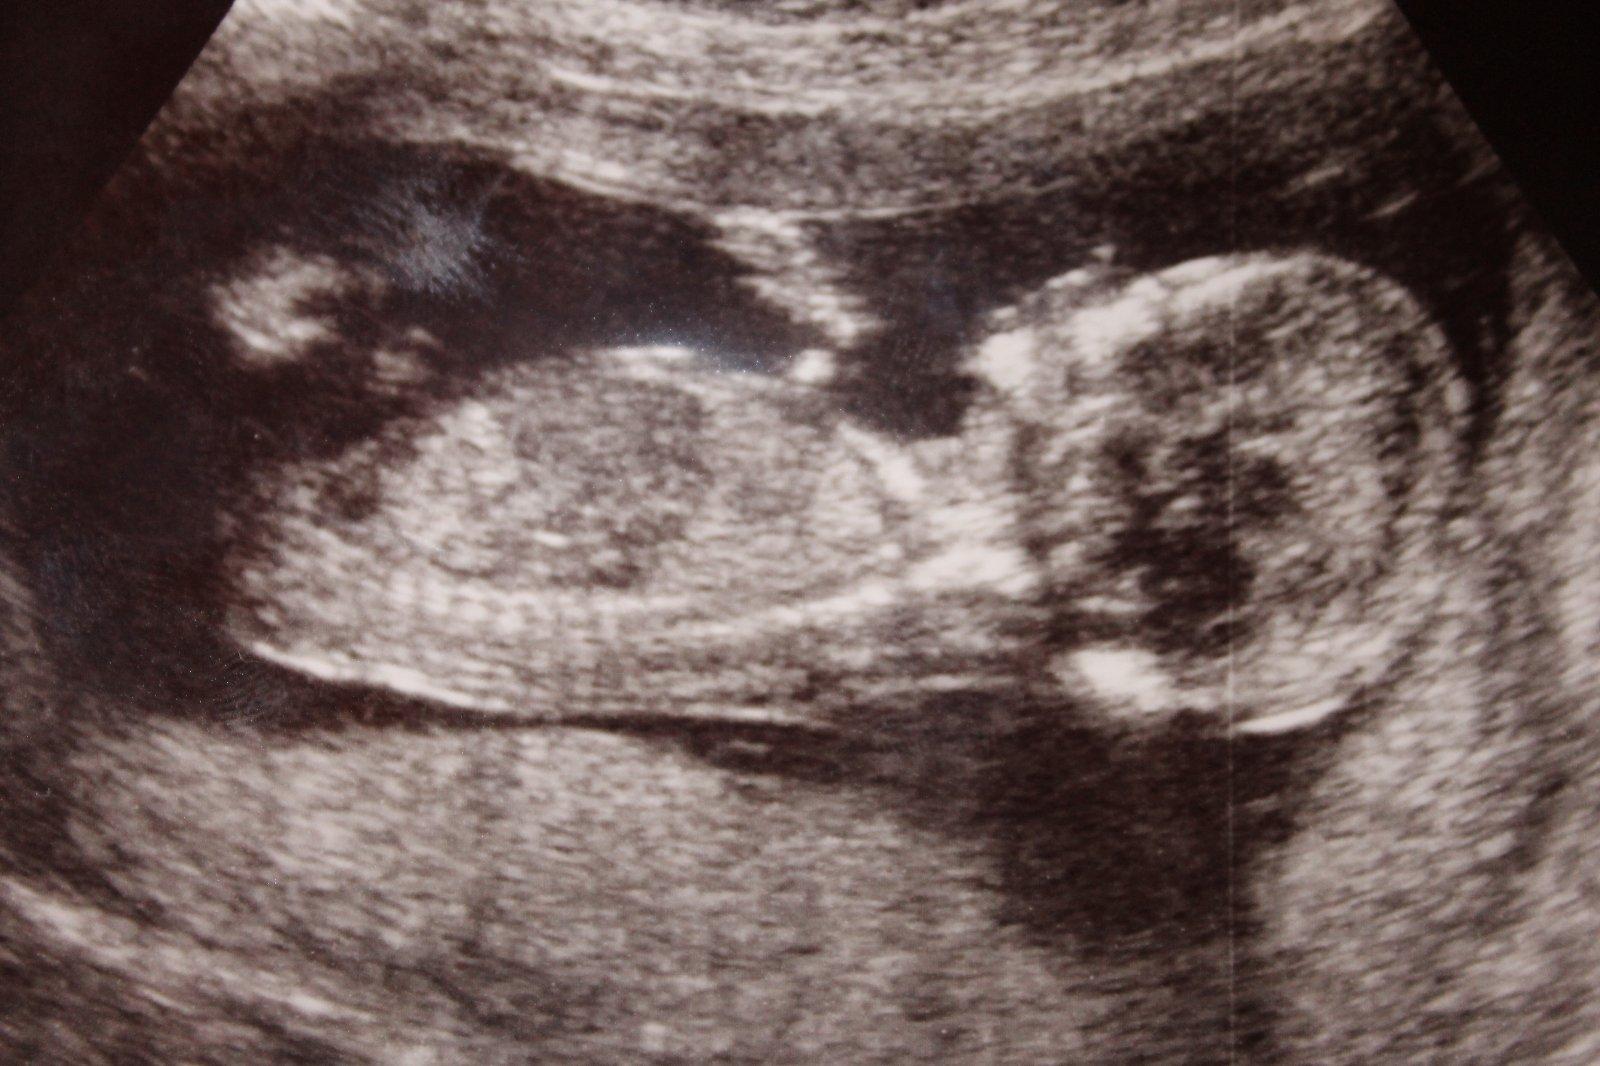

Ahojky, holky, kdyz zkoumali co cekate, tak to bylo asi podrobneji a priblizovali mimise? Mi v patek po dotazu, jedtli jse poznat, mimuse mela z boku celeho a pry ze kluk, byl ta videt jakoby pytlik, ale pochybuju, ze na konci 13 tt by tam byl a tak veliky, spis mi to prislo jako pup. snura.. :( uvidim ve stredu na kontrole, se poptam...

@kremrolka01 Ahoj prosim,poznala by jsi z fotky z Utz zda by to mohla byt holcicka či klucik? Na screeningu nám doktor rekl 80%holcicka...😁 tak jestli jsi to na utz mela jinak.Dekuji moooc.

@ramottka ahoj,mohu otravovat a zeptat se zdá z fotky z Utz poznáš zda holcicka či klucik když poslu?😀 dekuji moooc